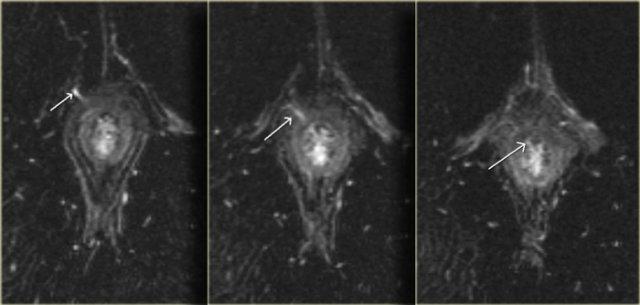

Bên trái là hình ảnh cắt ngang chuỗi xung T2W và T2W kết hợp xóa mỡ của một đường rò xuyên cơ thắt.

Khuyết hổng qua cơ thắt trong và cơ thắt ngoài ở vị trí 6 giờ hiện rõ và nổi bật hơn trên hình ảnh xóa mỡ.

Bên trái là hình ảnh cắt ngang chuỗi xung T2W xóa mỡ của một đường rò xuyên cơ thắt với lỗ mở niêm mạc ở vị trí 11 giờ.